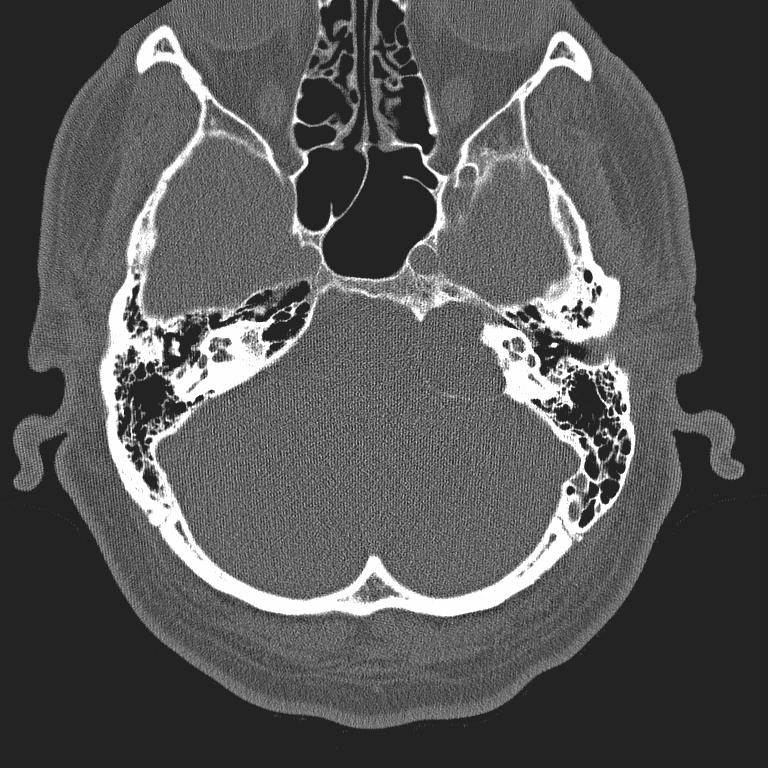

HRCT excels in the evaluation of air spaces and fine bone structures - including hearing ossicles - of the temporal bone. HRCT is primarily performed at submillimeter intervals, which allows reconstructions in all three planes.

High-resolution CT (HRCT) is primarily performed at submillimeter intervals, and excels in the evaluation of bone and air space anatomy, and in disorders of the temporal bone, hearing ossicles and air cells. However, its role is limited in soft tissue pathology, mucosal thickening and fluid accumulation. In abnormalities of the middle ear HRCT is superior to MRI in most cases (except in tumours). HRCT is the modality of choice in conductive hearing loss, otoslerosis, and malignant otitis externa in diabetic patients and in surgery planning. One of the disadvantages of HRCT – especially in children - is the relatively high radiation dose to which the eye lenses are sensitive. Differentiation between hypodens structures filling the ear and air cells also might be problematic. HRCT’s role is also limited in the early detection of intracranial complications. Intravenous contrast administration in HRCT is not possible due to technical diffculties.

To evaluate soft tissue pathology, mucosal thickening and fluid accumulation, MRI is recommended, especially in the middle and inner ear. MRI plays an important role in inflammatory and tumorous processes, and in their intracranial and extracranial complications. MRI is the modality of choice to assess extracranial and intracranial complications of inflammatory ear disease, including most commonly epidural and cerebral abscesses and sinus thrombosis secondary to chronic otitis media. Examination of the pontocerebellar angle in sensorineural hearing loss is performed by a special thin-slice T2W MRI sequence and postcontrast T1W MRI, since these sequences are capable to detect acoustic neurinoma, while HRCT cannot visualize this abnormality. In some complex diagnostic cases both CT and MRI are needed for accurate diagnosis.

1. image: Patient with sensorineural hearing loss and tinnitus. MR-study (T2, precontrast T1 and postcontrast T1) reveal a mass in the left pontocerebellar angle without significant contrast enhancement. HRCT proves that the mass arises from the petrous pyramid, suggesting cholesterol granuloma. (Asklepios Klinik Altona, Hamburg)